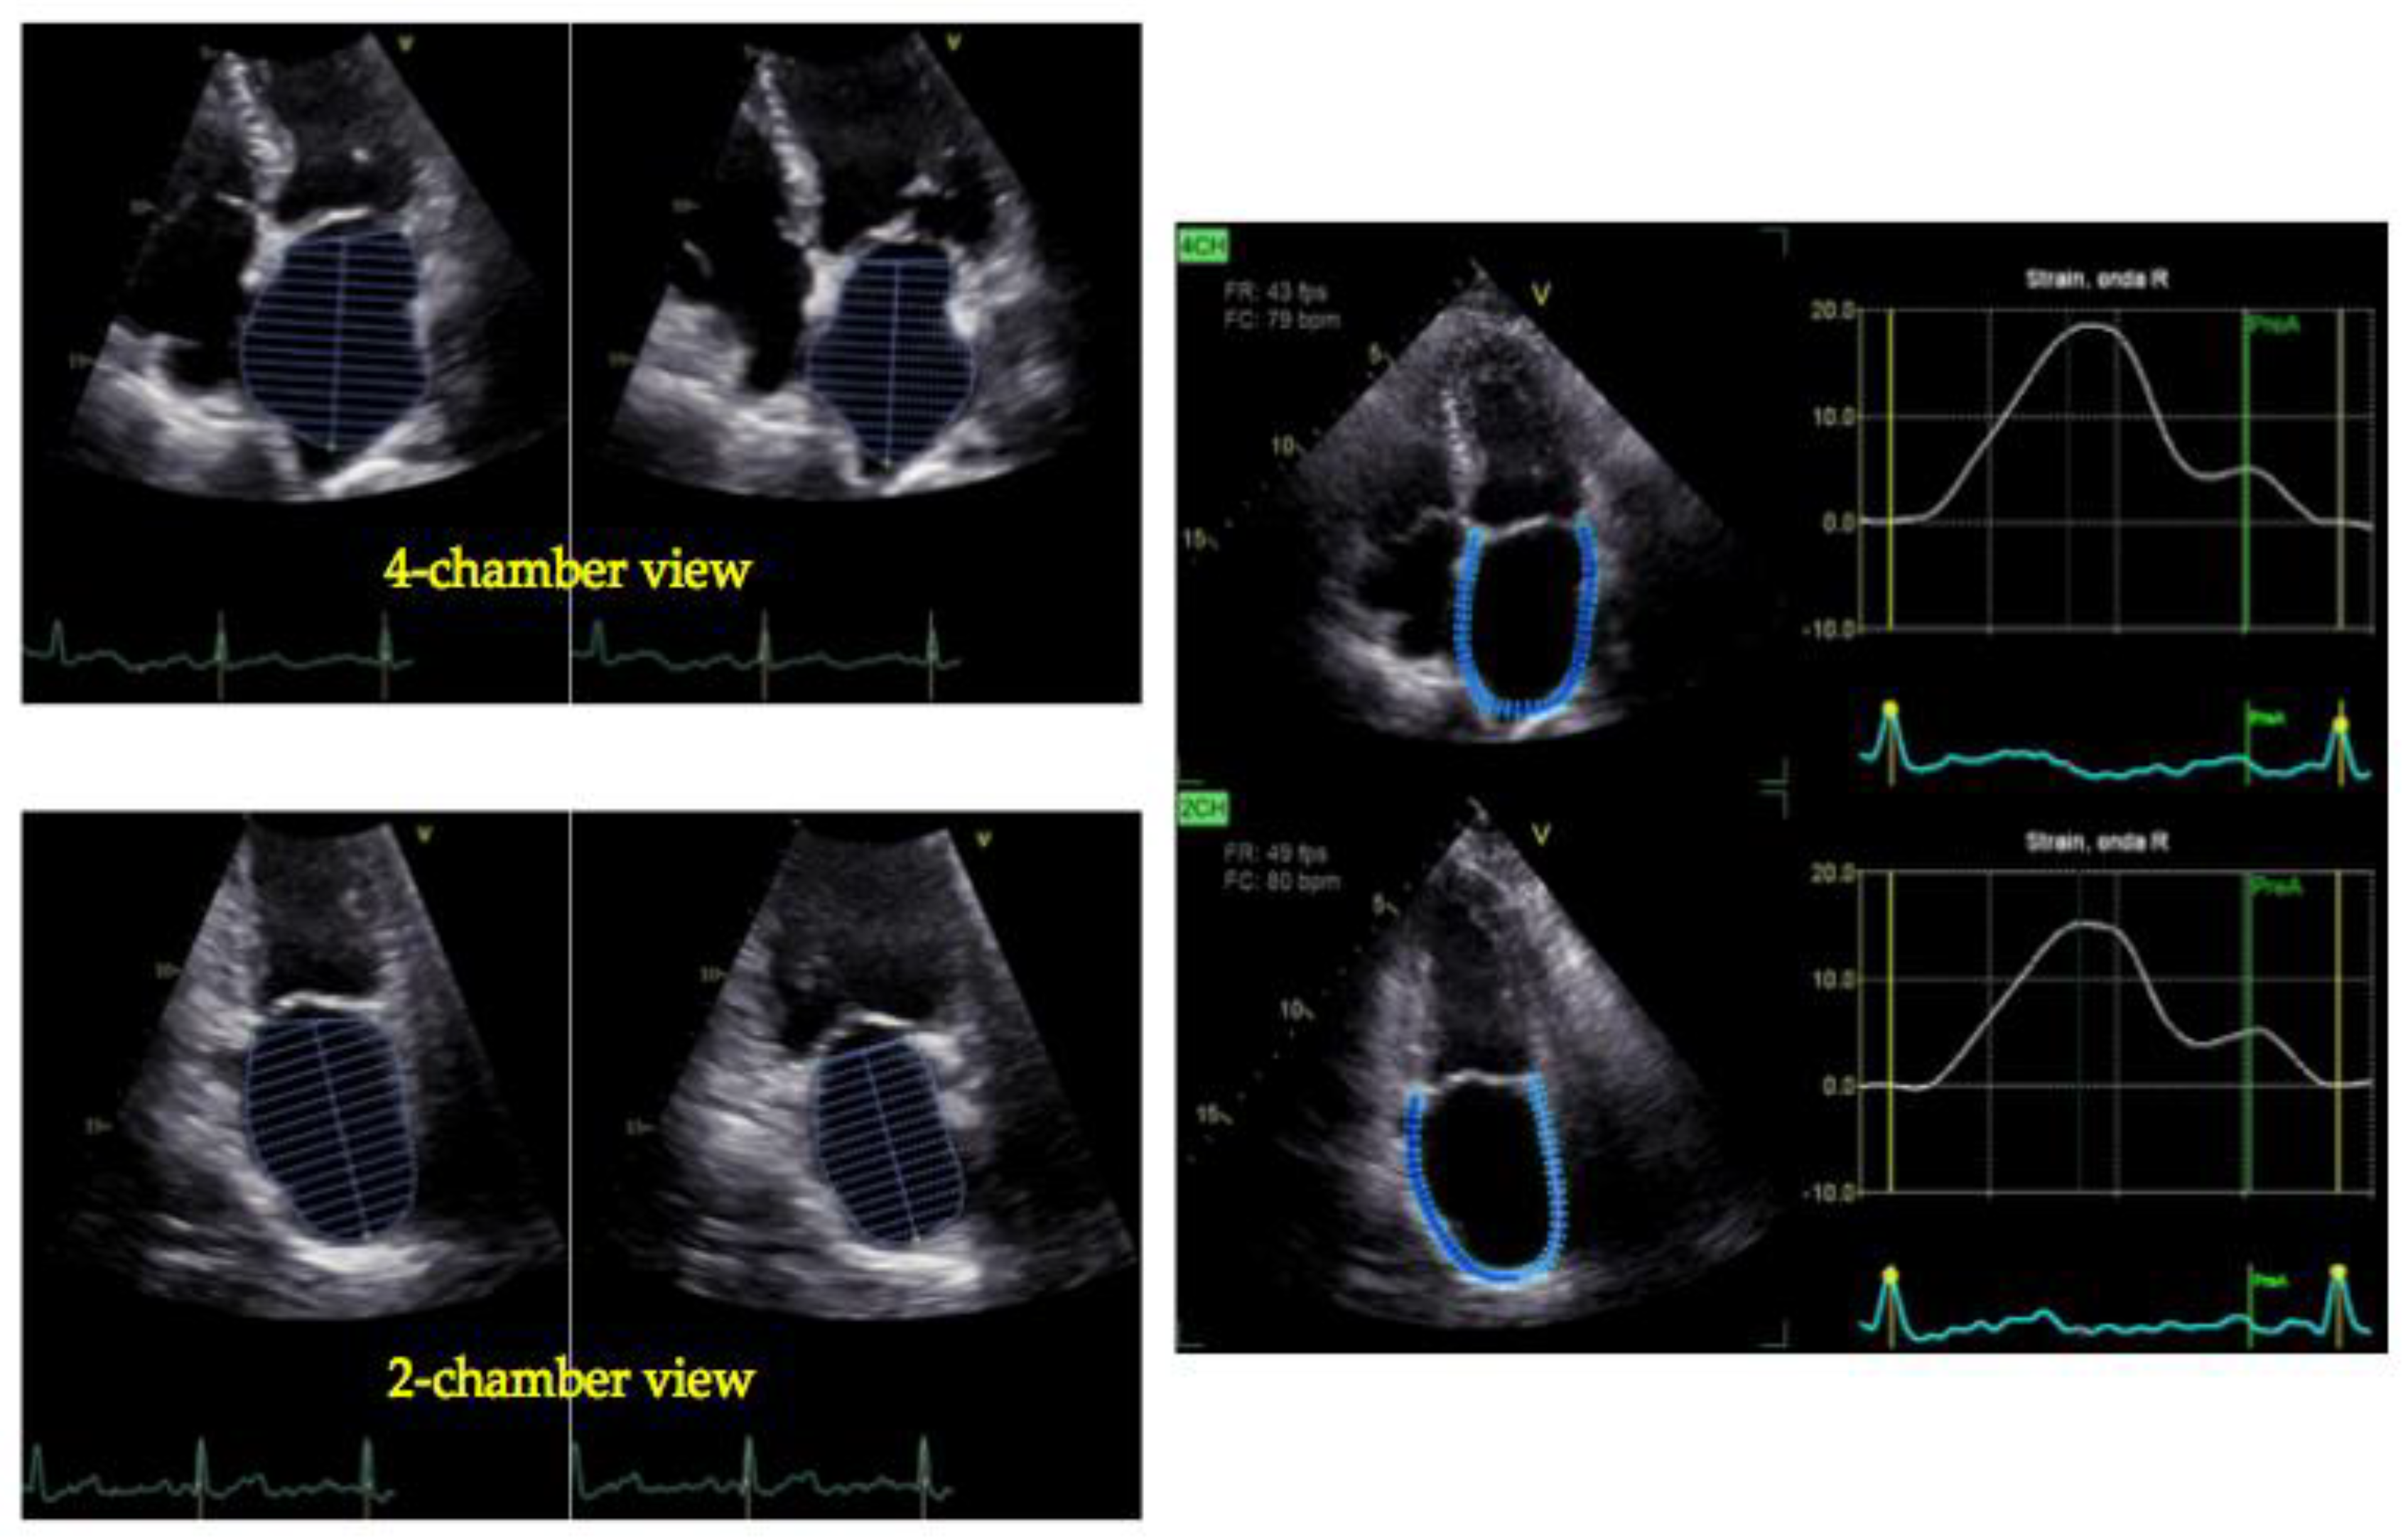

4. Peak Atrial Longitudinal Strain